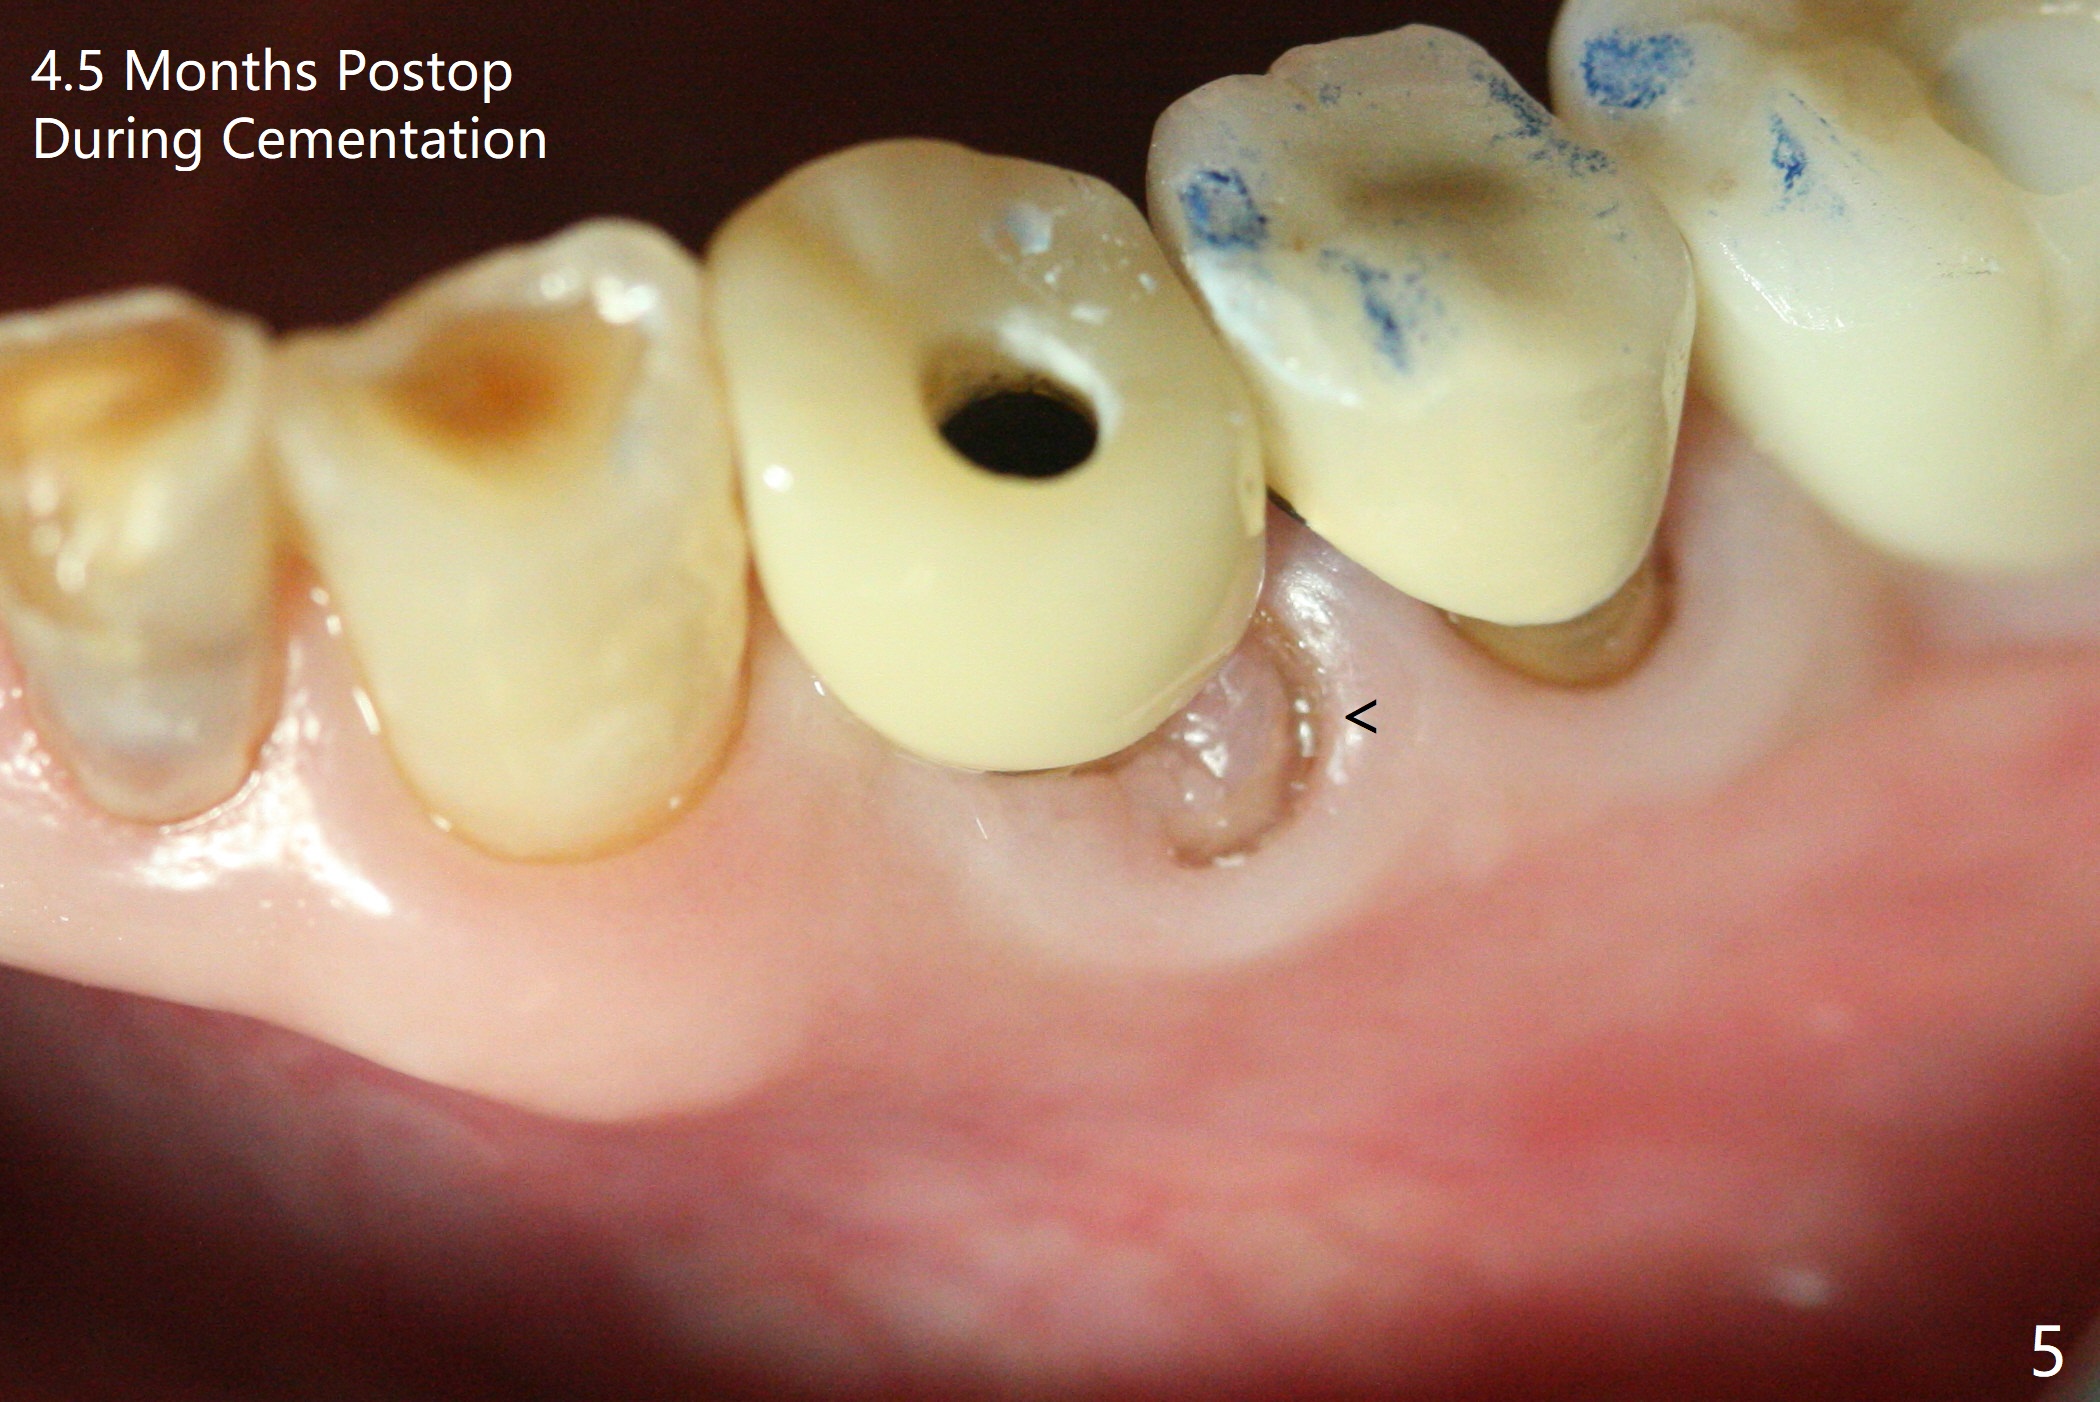

Extraction of the fractured tooth at #21 is as difficult as #19 (requiring incision). Because of the long root and hemorrhage, the apex of the tooth (Fig.1 black *) and a thin layer of the buccal shield (white *) remain when osteotomy is initiated. Due to hard bone, a 3.8x11.5 mm implant achieves insertion torque of ~35 Ncm (Fig.2); with placement of a 4.5x4(3) mm abutment, an immediate provisional is fabricated. There is limited remaining space for bone graft. The patient will return for final restoration 4 months postop; the buccal plate will be expected to have not collapsed! The implant seems to be osteointegrated, while the root piece (socket shield *) is exposed 4 months postop (Fig.3). The socket shield seems to be harmless, difficult to trim without local anesthesia and associated with no buccal plate concavity (Fig.4,5 <). With socket shield at #21, the crown looks normal, whereas the one at #19 without socket shield looks long, suggesting vertical bone loss early postop (before restoration, Fig.6).没有牙根处,角化龈少(图七,与术前(图八)对比)。